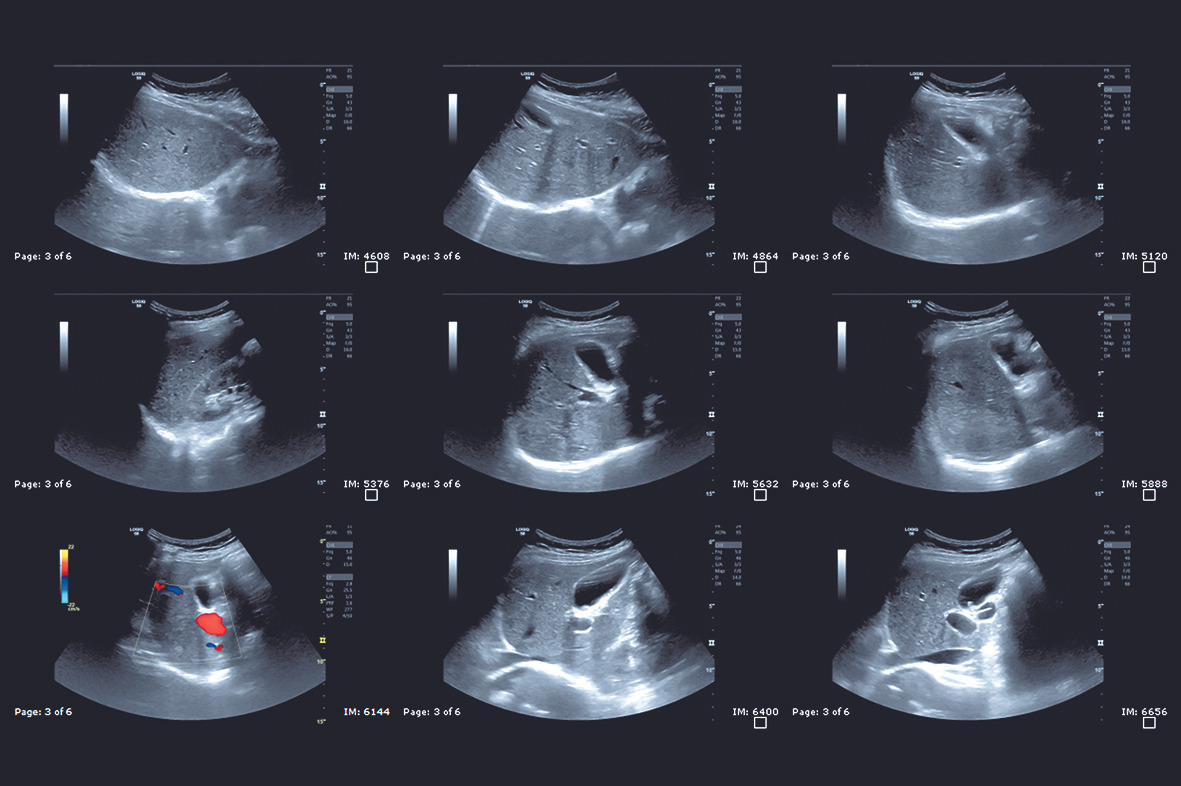

- 탐색: 탐촉자를 위·아래·양옆으로 이동하며 각 장기를 촬영

- 체위 변화: 장기 위치에 따라 옆으로 눕거나 숨을 들이쉬게 요청

- 실시간으로 장기 구조 확인 가능

- 간단한 구조적 이상, 종양, 결석 탐지에 유용